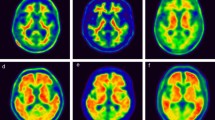

The concordance rate for visual assessment between FBB and FMM was 94.4% (101/107, Fig. 1 and Table 2). In six participants with discordant results, all were FBB-negative and FMM-positive. In Fig. 2, case 1 represents the participant who was FBB-negative but FMM-positive based on visual assessment although SUVR and dcCL positivity were both negative. Case 2 represents the participant who was FBB-negative but FMM-positive based on visual assessment although SUVR and dcCL positivity were both positive.

FBB and FMM uptake in participants. Four representative cases of FBB and FMM PET and FLAIR MRI are shown. Case 1 represents the participant who was FBB-negative but FMM-positive based on visual assessment although SUVR and dcCL positivity were both negative. Case 2 represents the participant who was FBB-negative but FMM-positive based on visual assessment although SUVR and dcCL positivity were both positive. Case 3 represents the participant whose visual assessment was negative but SUVR and dcCL positivity were both positive for FBB and FMM. Case 4 represents the participant who was positive based on visual assessment but SUVR and dcCL positivity were both negative for FBB and FMM. The Scale bar indicates standardized uptake values (SUVs). The arrow indicates focal uptake of FMM in the cortex. Abbreviations: FBB, 18F-florbetaben, FMM, 18F-flutemetamol; FLAIR, fluid-attenuated inversion recovery; SUVR, standardized uptake value ratio; dcCL, the Centiloid (CL) units using the direct comparison of FBB-FMM CL method.

For FBB, visual assessment and SUVR classification did not match in seven of 107 participants (Fig. 1): five participants were visually negative but SUVR-positive, and two participants were visually positive but SUVR-negative. For FMM, disagreement between visual and SUVR classification was found in nine of 107 participants: four participants were visually negative but SUVR-positive, and five participants were visually positive but SUVR-negative. In Fig. 2, case 3 represents the participant in which the visual assessment was negative but the SUVR classification positive for both FBB and FMM. In Fig. 2, case 4 shows the participant for whom the visual assessment was positive but the SUVR classification was negative for both FBB and FMM.

In addition, both FBB and FMM showed high concordance rates between visual assessment and SUVR cut-off categorization for Aβ deposits (93.5% in FBB and 91.6% in FMM). The findings were consistent with previous studies in which the accuracies of visual assessment and quantitative assessment in evaluating Aβ positivity were comparable2,3. FBB (91%–96%)4 and FMM (95.3%)13 showed high agreement between visual assessment and SUVR quantification. In a previous study, disagreement among cases was possibly explained by severe brain atrophy13, however, severe atrophy was not observed in the present study. Most of the discrepancies between visual assessment and SUVR results were due to amyloid focal uptake in both FBB and FMM as shown in Fig. 2 case 4.

Why some FMM images were over-estimated is not evident. However, unlike FBB, FMM was evaluated based on a color scale, which might have affected the reading. Apparently, experts conducting visual analysis on a color scale tend to over-estimate the reading. In Fig. 2 case 1, which presents FMM-positive based only on visual assessment, there was focal uptake toward the lateral temporal cortex, while there was a visually distinguishable difference in signal activity between grey and white matter in the same FBB area. In the present study, signal differences were better discriminated using FBB than FMM. In addition, FMM appears slightly blurrier than FBB, which might be another reason for the discrepancy. Alternatively, when pathology and visual reading in FMM were compared in previous studies, more false-positives were identified with visual reading, apparently due to the presence of diffuse plaques14. In addition, FMM binds to both neuritic and diffuse Aβ plaques14,17. Both types of plaque generally co-exist in the neocortex of AD patients and FMM PET signal corresponds predominantly to neuritic plaques but is affected by the presence of diffuse plaques18. The additional FMM PET signal from diffuse Aβ plaques can result in positive PET reads, which might contribute to the false positivity of FMM seen in this study in addition to the aforementioned factor.